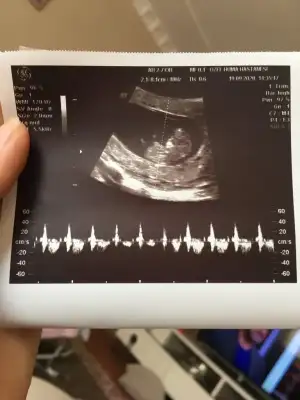

@Ikra meyra daha önce size bebeğimin ultrason fotosunu atmıştım kafa yapısından erkeğe benzetmiştiniz haftasonu muayenede doktorum çıkıntıdan dolayı erkeğe benzettiğini söyledi videodan ekran görüntüsü attım sizce de erkek mi 😊🌸 11+3 karından ultrason görüntüsü

Bakin şimdi buna erkek demis parlak olunca siz olunca kiz demekki paralel olunca erkek normal olunca kiz ozaman seni kiz Princesssss Princesssss bilemedim😄

8+4 bana kiz dedin😂ben bacak gormuyom ki paralelmi die bakayim😂😂ya pazartesi 10.haftaya baslicaz arkadas zman gecmio cok merak ediorm cinsiyetin8

Eklentiler

• 20200914_153822.webp

20200914_153822.webp

19,6 KB · Görüntüleme: 63